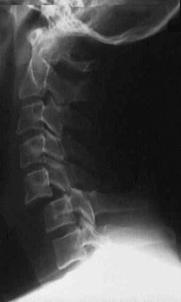

TRAUMA CERVICALA

Incidenta laterala Incidenta

laterala Incidenta

antero-posterioara

Aspect normal Imagine

incompleta Aspect

normal